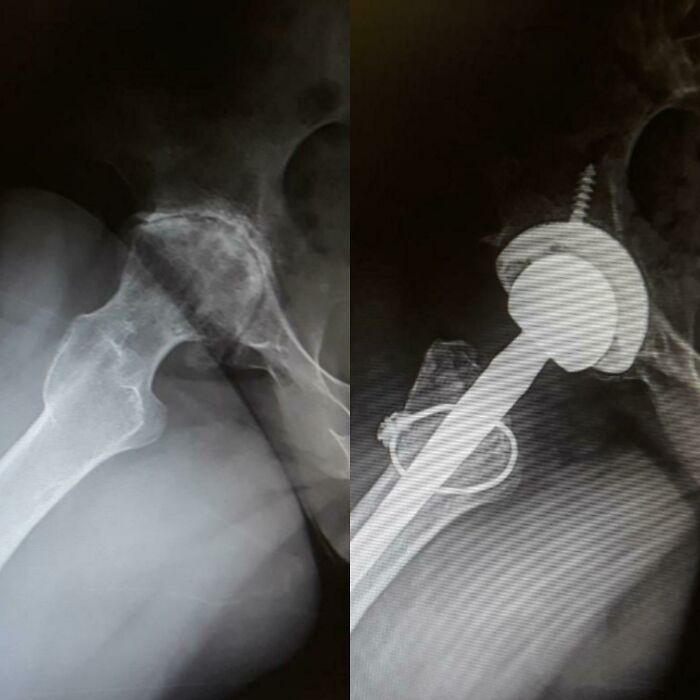

Before And After Hip Replacement Surgery